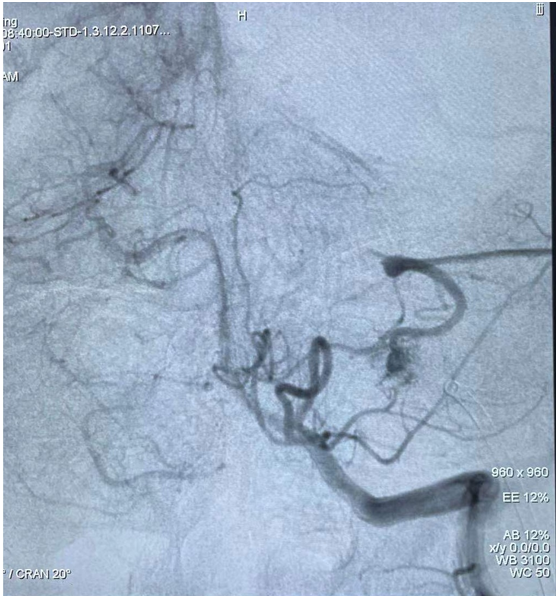

該患者因“突發(fā)頭痛、頭暈伴惡心嘔吐3天”入院,發(fā)病時就診當?shù)蒯t(yī)院,行頭顱CT顯示左側(cè)小腦出血,后轉(zhuǎn)我院進一步治療。在我院完善頭顱磁共振后考慮血管性疾病出血,給予全腦血管造影顯示左側(cè)小腦動靜脈畸形?;颊邽槟贻p女性,結(jié)合病情,家屬要求選擇創(chuàng)傷小、無手術(shù)疤痕的介入治療。神經(jīng)外科團隊積極完善術(shù)前準備,認真閱讀全腦血管造影圖像后制定了嚴密的手術(shù)方案。術(shù)中,科室團隊在傳統(tǒng)介入手法進行操作的基礎(chǔ)上,同時建立動脈及靜脈通道,動脈栓塞時因栓塞劑返流嚴重,立即采用備用方案經(jīng)靜脈途徑,由畸形團出口處反向注入栓塞材料,畸形團栓塞效果確切,完全未顯影,供血動脈及引流靜脈完好,基本達治愈效果?;颊咝g(shù)后神志清楚,無顱神經(jīng)受損癥狀,四肢活動正常,術(shù)后5天痊愈出院。

圖2:全腦血管造影示:左側(cè)小腦動靜脈畸形